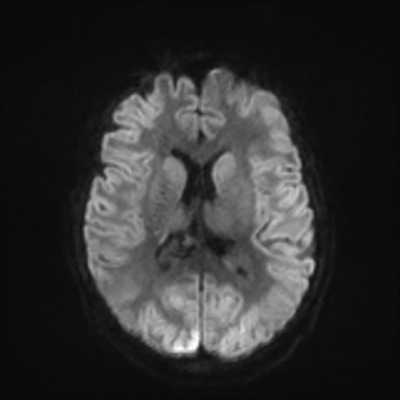

MRI brain (DWI)

You can clearly see diffuse cortical and basal ganglia diffusion restriction, and that of his deep cerebellar nuclei as well. The right occipital lobe abnormalities are a little more prominent, but then you remember that he is known to have had a right occipital stroke weeks ago.